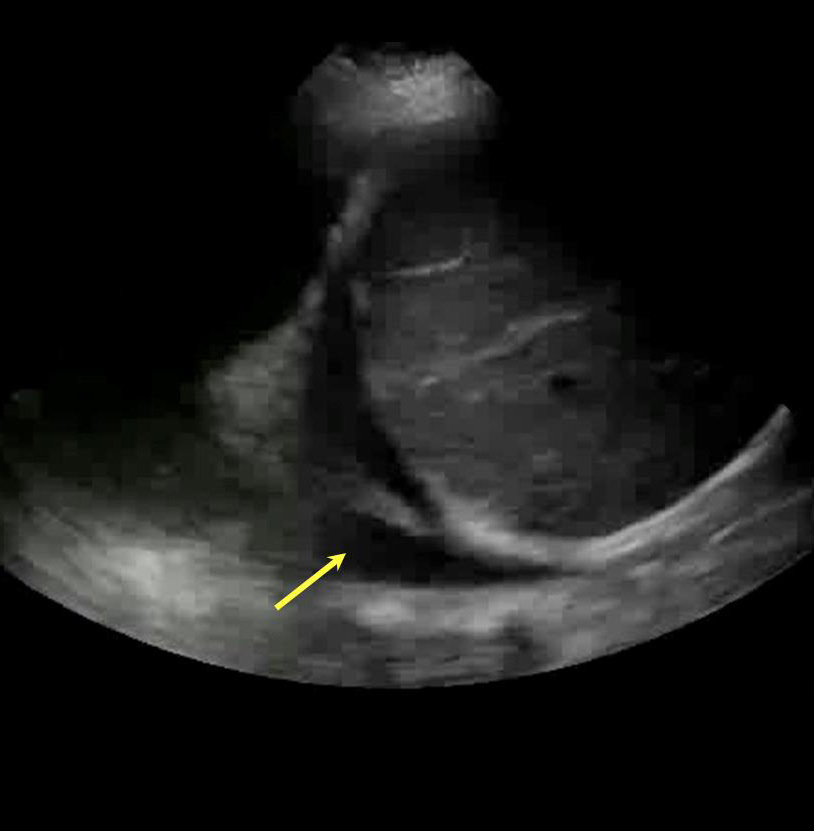

Lung Pleural Effusion Image

Yellow Arrow: Pleural Effusion